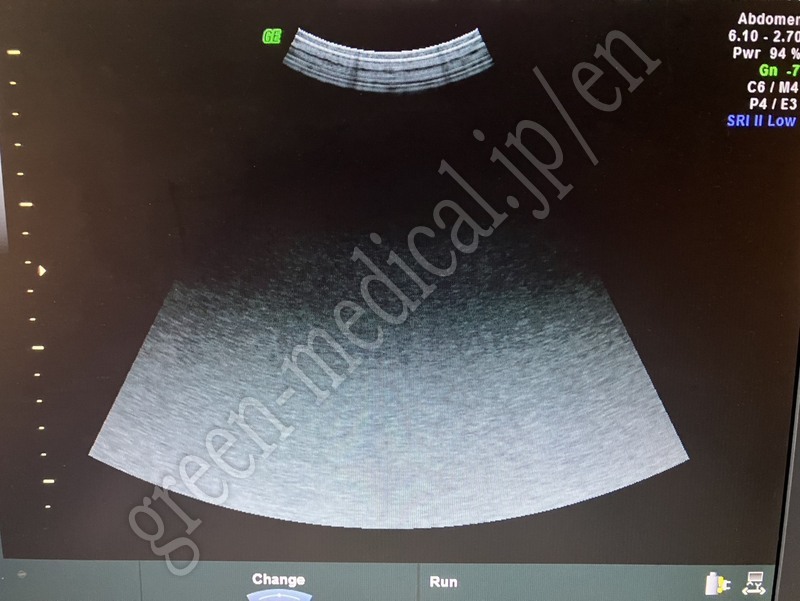

Portable Ultrasound Voluson e

GE Healthcare

Voluson e

114663